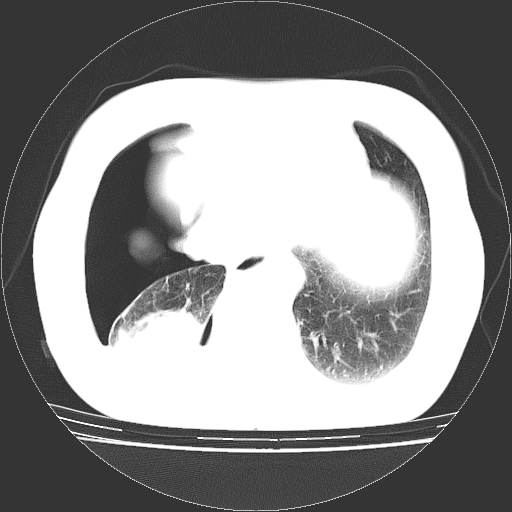

以下是引用zhangzhongshou在2008-3-22 12:52:00的发言:[br]1、右侧液气胸。[br]2、腹水。建议进一步检查。

以下是引用鲁巨ct在2008-3-22 14:10:00的发言:[br]1、右侧液气胸,右中下叶节段性不张。[br]2、腹水,建议上腹部ct检查

以下是引用zjzjr在2008-3-22 17:19:00的发言:[br]1、右侧液气胸,右下叶节段性不张。[br]2、腹水,建议上腹部ct检查